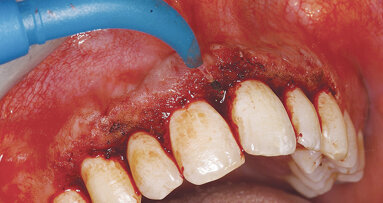

Obr. 4: Počáteční chronická léze – parodontální tkáň: Zvýšená retencezubního mikrobiálního povlaku, rozpad periodontálních vazů a tvorba ulcerací na epiteliální výstelce, počátek resorpce kosti. Buněčná úroveň: Zvýšený počet neutrofilů, makrofágů a dalších. Biochemická úroveň: Zvýšená prozánětlivá aktivita cytokinů, arachidonová kyselina pokračuje v produkci prostaglandinu, uvolňuje se i MMP.

Obr. 5: Pozdní chronická léze – parodontální tkáň: Apikální migrace patogenních mikroorganismů jako je P. gingivalis, další rozpad periodontálních vazů a zvýšená tvorba ulcerací na epiteliální výstelce, závažná resorpce kosti. Buněčná úroveň: Více neutrofilů, makrofágů a dalších. Biochemická úroveň: Zvýšená hladina prozánětlivých cytokinů reguluje uvolnění MMP (podílejících se na kostní resorpci a degradaci kolagenu). Kolagenové fragmenty poskytují výživu patogenním mikroorganismům. Arachidonová kyselina pokračuje v produkci prostaglandinu.